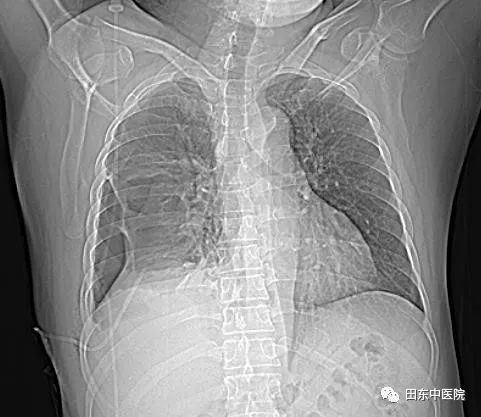

中午12点,一位体型肥胖病人走进了医生办公室,刚好交班结束的我接待了他,他自诉已胸痛了10天有余,先前因腰痛一直在院外治疗,没有好转遂到我院进行进一步的检查。详细了解完其病史后,我为其完善了体格检查:右侧胸胁部疼痛,呈持续性胀痛,有胸闷、呼吸困难,发热畏寒。查体见双侧呼吸运动不对称,两侧触觉语颤不对称,右肺叩诊浊音,右肺呼吸音消失。结合先前他在门诊做过的B超及后续补充的胸部CT结果,发现病人右侧胸腔有大量积液,为了解积液性质及缓解积液对肺脏的压迫,遂给病人行胸腔穿刺置管术,把胸腔里的积液引流出来。过程很顺利,术中抽出了约5000ml伴有腐臭气味的咖啡色脓液,术后病人的疼痛症状得到了极大的改善。

术后